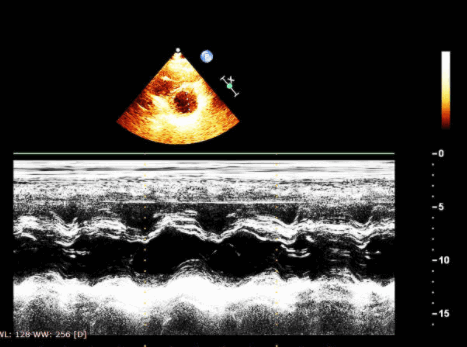

Функция левого желудочка и фракция выброса (ФВ)

Левожелудочковая слабость вызывает застой крови в малом круге и кардиогенный отек легких.

Чтобы оценить сократительную функцию миокарда ЛЖ, применяют критерий фракции выброса.

ФВ 60% означает, что при сокращении ЛЖ выбрасывает 60% от общего объема принятой крови.

Общепризнанная градация фракции выброса от гипердинамической до значительно сниженной:

Чтобы дать качественную оценку ФВ, замечайте движение стенок ЛЖ и передней створки МтКл.

Эхо-признаки удовлетворительной ФВ:

- в систолу стенки ЛЖ утолщаются >30% и хорошо сближаются;

- в диастолу передняя створка МтКл подбирается к перегородке.

Эхо-признаки неудовлетворительной ФВ:

- в систолу стенки ЛЖ немного утолщаются и слабо двигаются;

- в диастолу передняя створка МтКл практически не движется;

Рис. Фракция выброса ЛЖ нормальная. Рис. Фракция выброса ЛЖ умеренно снижена. Рис. Фракция выброса ЛЖ значительно снижена.